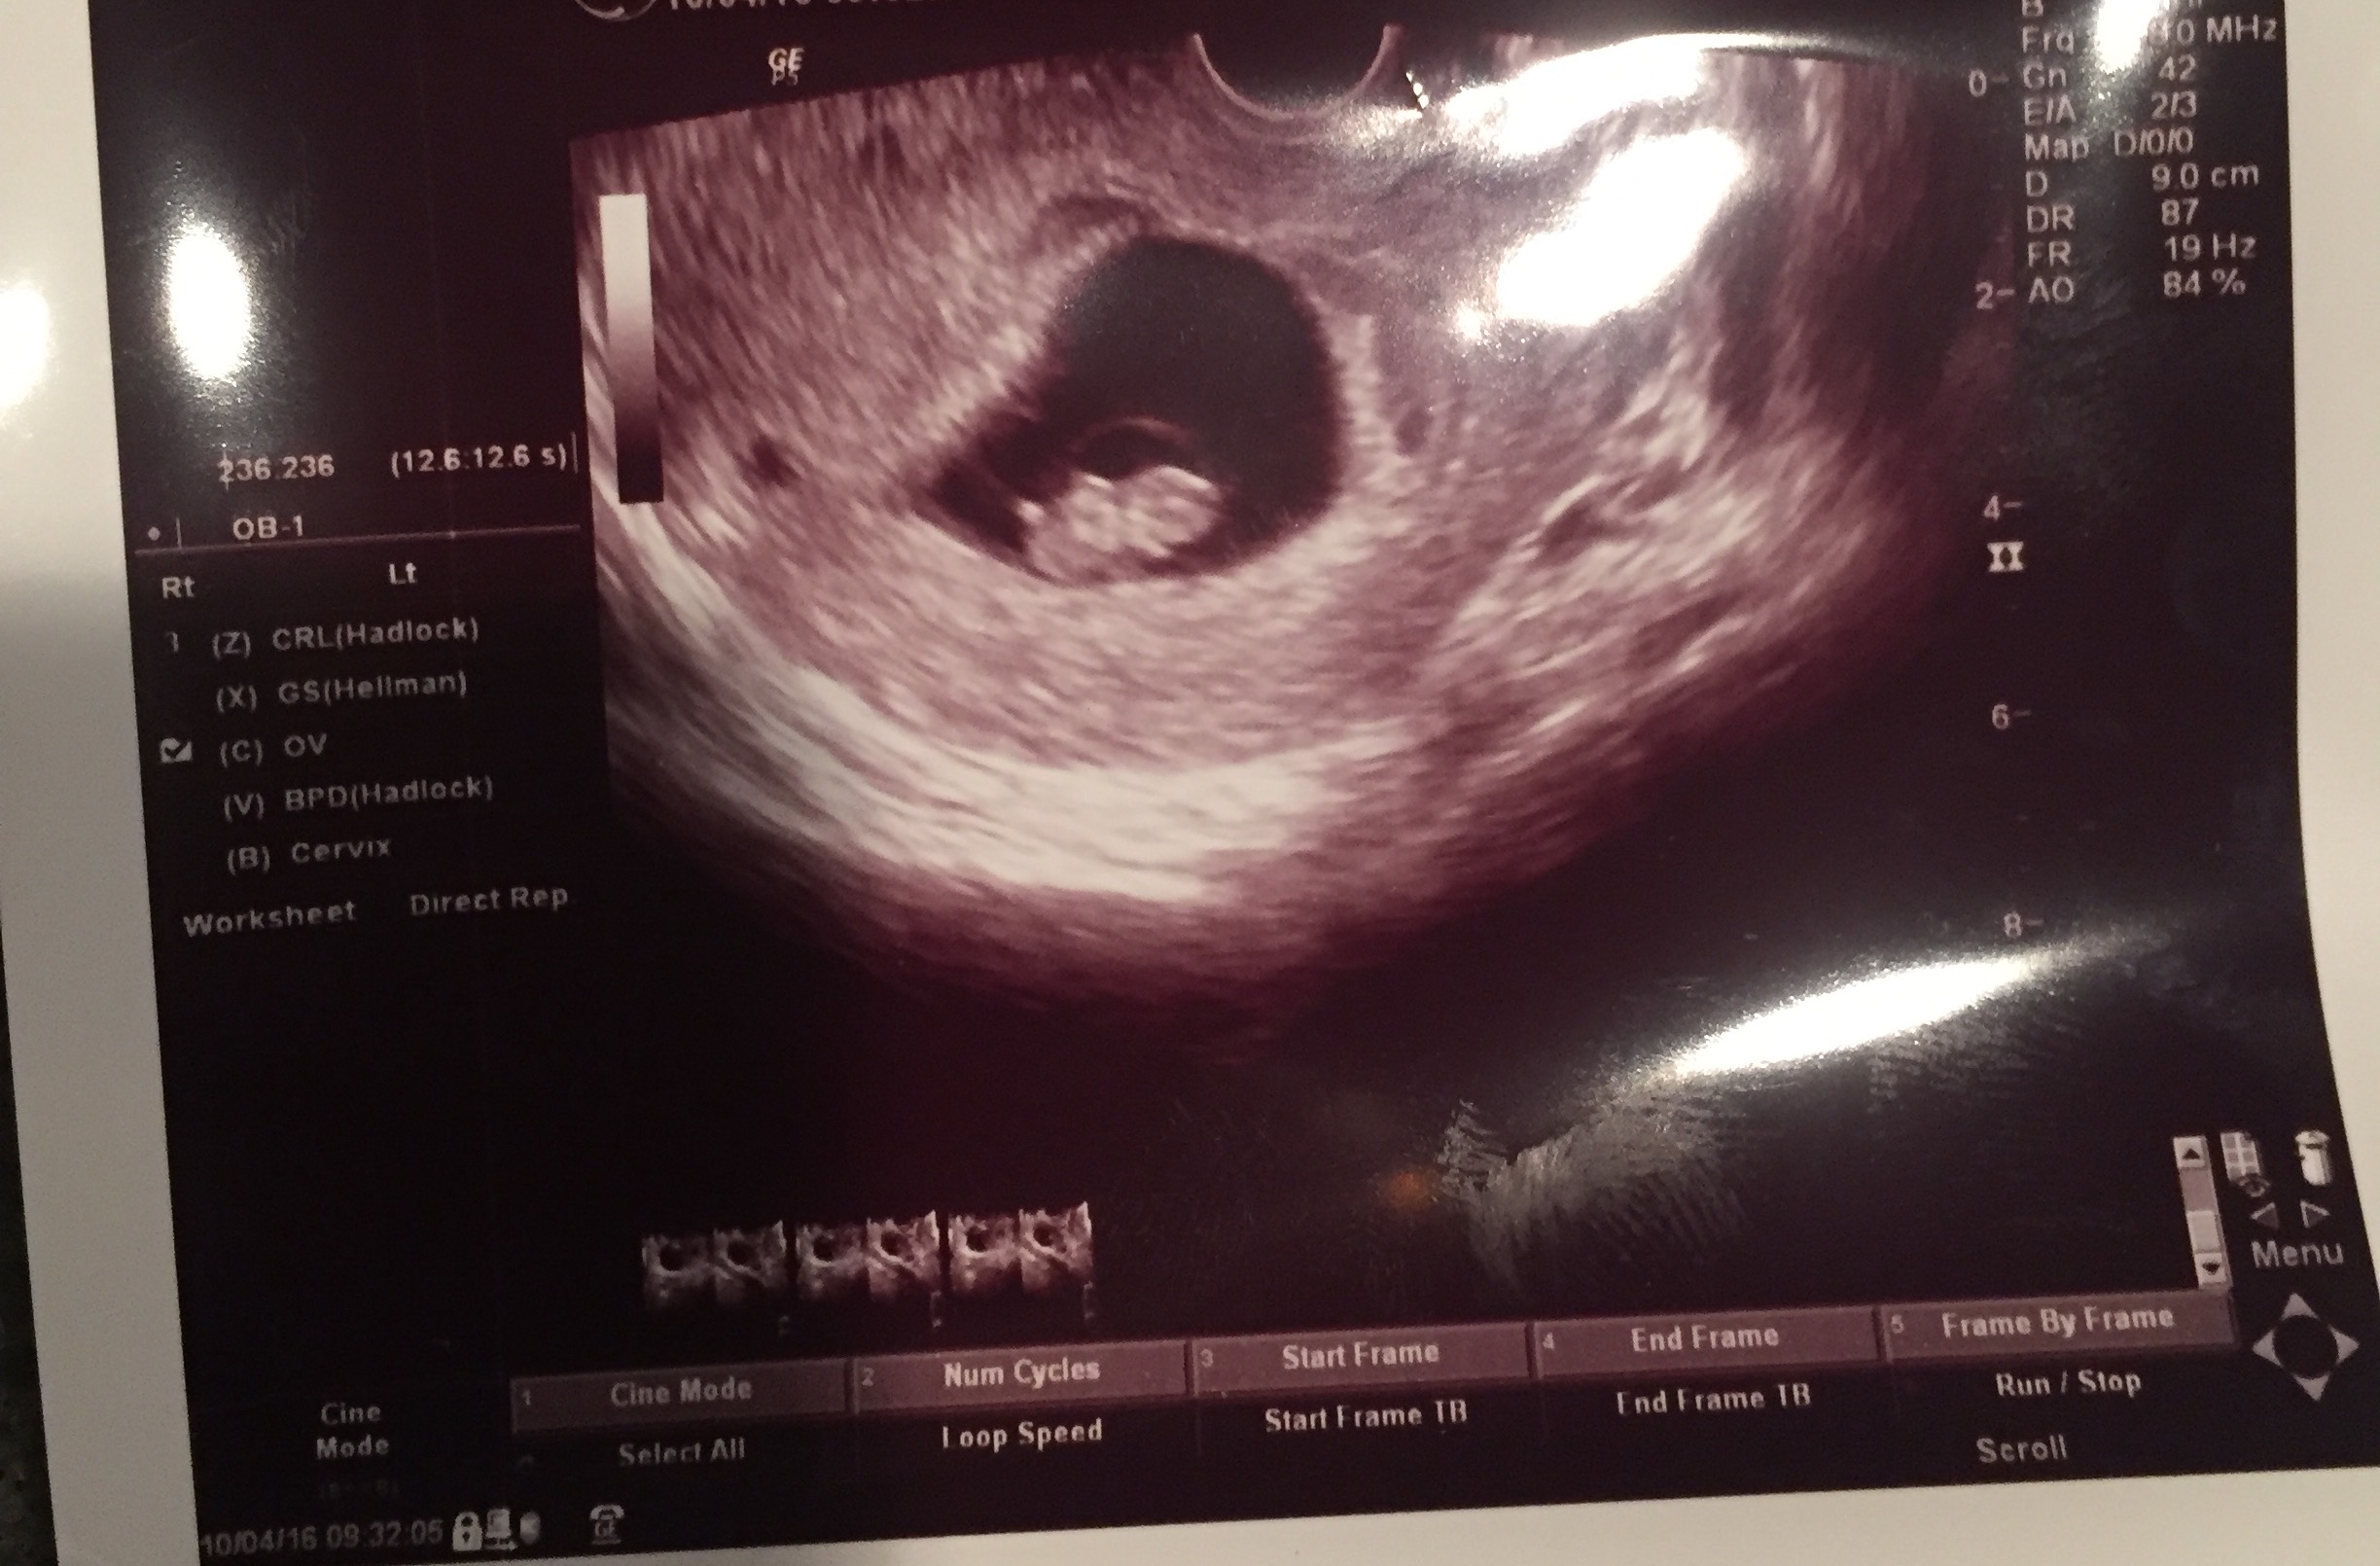

Can anyone guess my baby's gender based on ramzi theory? Here is my 8 wk USAttachment 33288

No guesses??